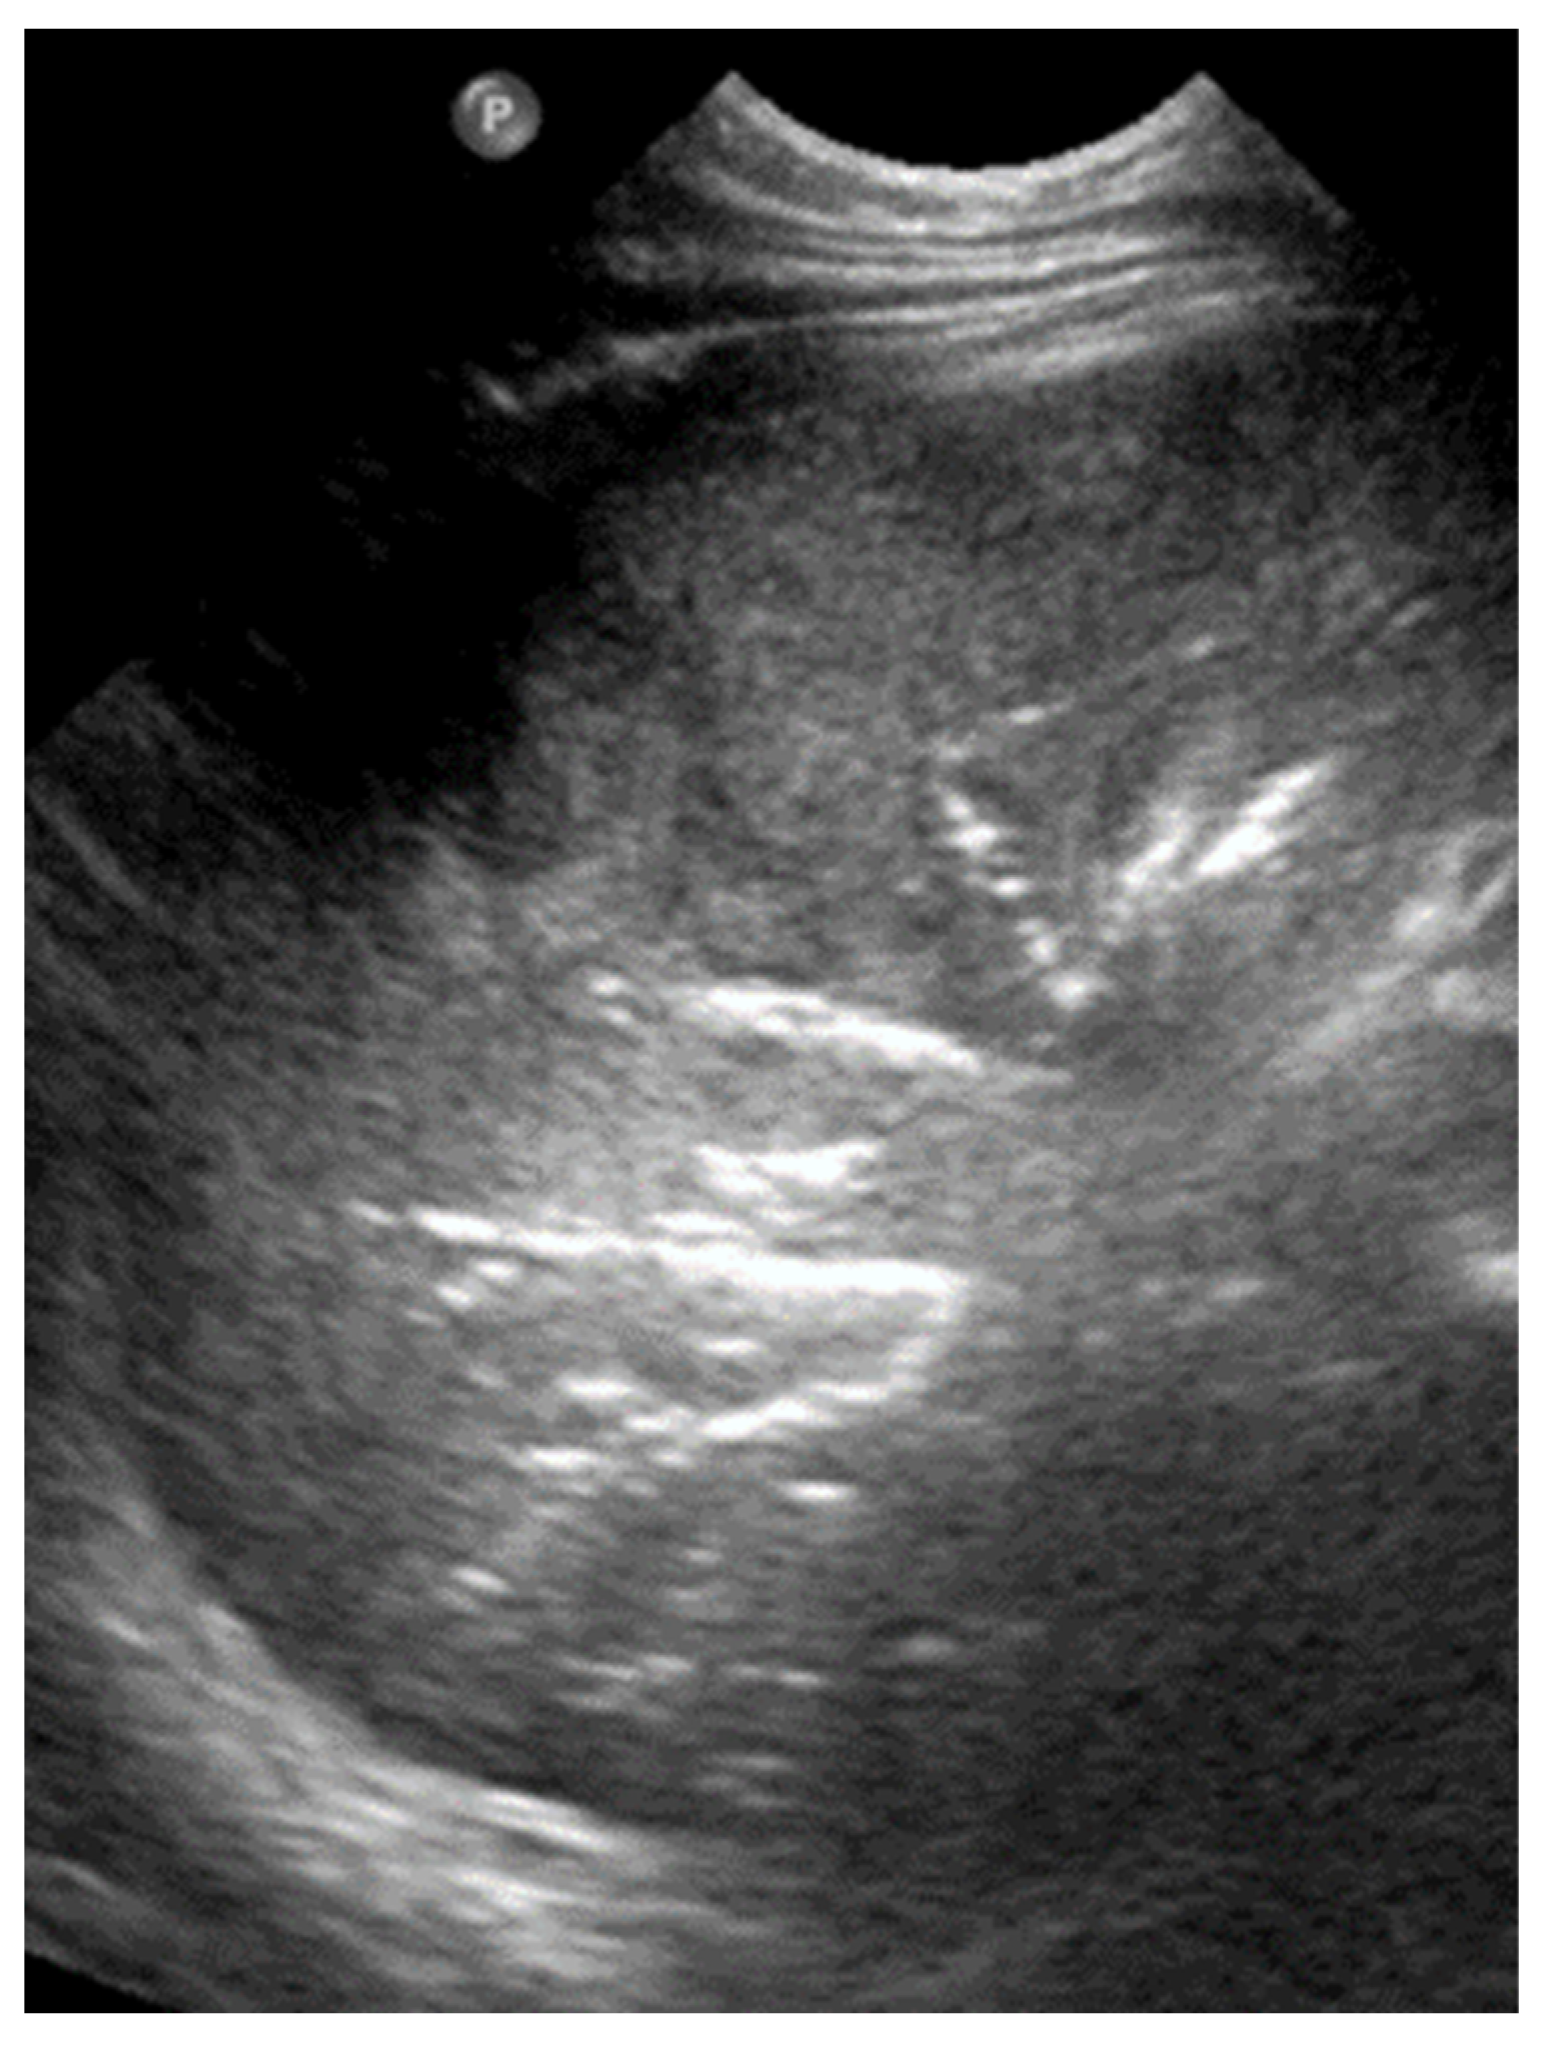

3.2.10. Pleural Effusion

Pleural effusion, defined as the accumulation of fluid in the pleural space, can be easily detected by LUS, which is highly sensitive and able to identify even small volumes of fluid (as little as 5–20 mL). In contrast, effusions greater than 175–250 mL must typically be present for the detection of pleural effusion by conventional chest X-rays, although lateral decubitus views may detect effusions of approximately 50 mL. A pure pleural effusion typically appears as an anechoic collection located between the parietal and visceral pleura, often seen as a clear, dark space (fluid) that allows for the visualization of underlying lung structures and diaphragm movement [13,20,35,54].

In contrast, complicated effusions may exhibit internal echogenicity due to the presence of fibrin, debris, or infection. Identifying the nature of the effusion, in other words whether it is simple effusion or complicated, is critical for clinical decision-making, and may help indicate the need for drainage, antibiotic therapy, or surgical intervention. Thus, LUS can be considered to play a pivotal role in both the diagnosis and management of pleural effusions, particularly in neonates and critically ill patients [10,23].